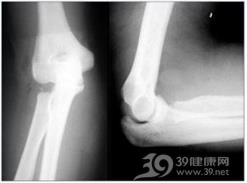

桡骨头骨折主要临床表现是肘关节功能障碍及肘外侧局限性肿胀和压痛。尤其前臂旋后功能受限最明显。拍摄肘关节前后位和侧位X线片可以诊断并能确定骨折类型。骨折的分类法能够代表损伤程度,并可提供选择治疗方法的依据。必要时可做双侧对比摄片,借此鉴别。

外伤史,肘关节功能障碍及肘外侧局限性肿胀和压痛。尤其前臂旋后功能受限最明显。X线能确诊骨折及分型。

肘关节正侧位X线能够显示骨折及分型。